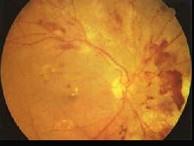

糖尿病眼部病变中导致失明的主要原因是 ( )A、视网膜小静脉扩张B、增殖性视网膜病变C、微血管瘤D、硬性渗出E、白内障

问题 糖尿病眼部病变中导致失明的主要原因是 ( )

选项 A、视网膜小静脉扩张 B、增殖性视网膜病变 C、微血管瘤 D、硬性渗出 E、白内障

答案 B